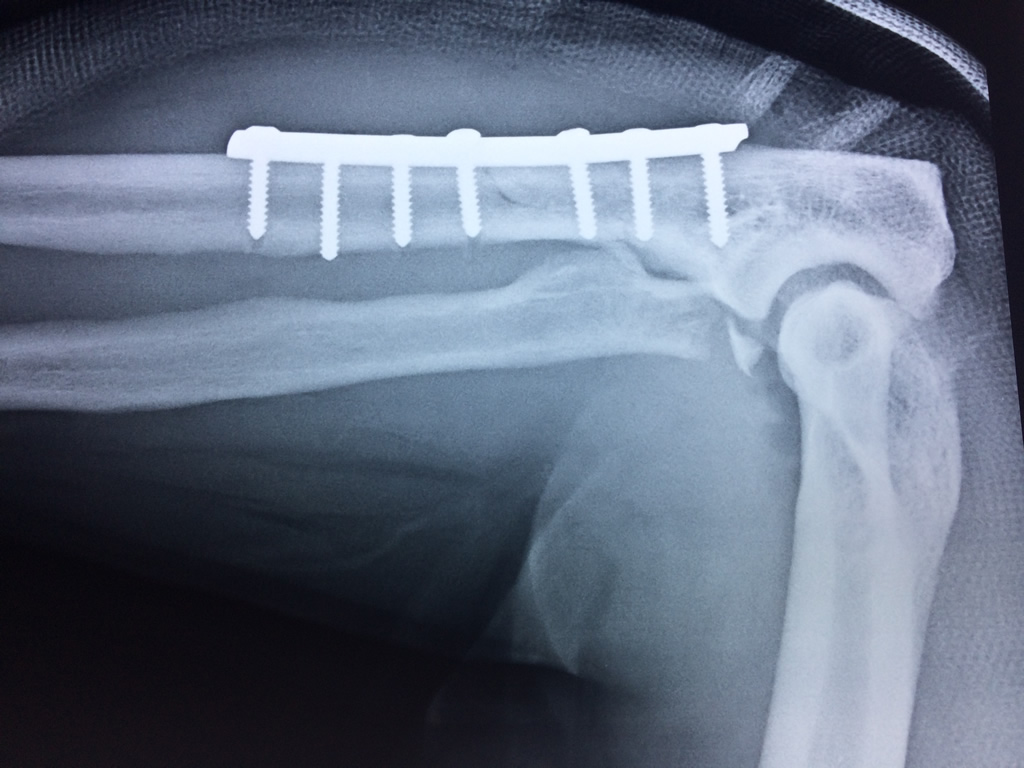

En anatomía humana, la articulación del codo es la que une el brazo con el antebrazo, conectando la parte distal del hueso húmero con los extremos proximales de los huesos cúbito y radio.

La articulación principal que constituye el codo se denomina humero radio-cubital y puede dividirse en dos partes bien diferenciadas, la articulación humero-radial y la humero-cubital.

Por otra parte el cúbito y el radio forman también una articulación entre si en las proximidades del codo, la cual se denomina articulación radio-cubital proximal.